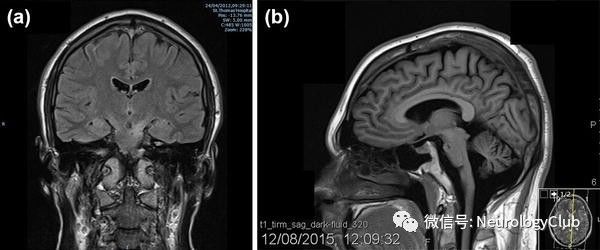

(图7:a:急性期FLAIR可见左侧中脑高信号病灶;b:3年后复查T1WI可见脑干和小脑萎缩)